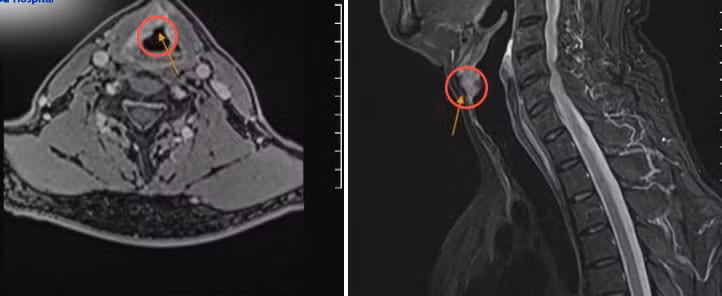

Kết quả sinh thiết khối u ghi nhận ông ung thư thanh quản dạng biểu mô tế bào vảy. Kết quả chụp MRI ghi nhận tổn thương ở thanh quản ngang mức dây thanh bên phải, kích thước 20x18x14 mm, lan rộng vào sụn giáp bên phải bờ bên trong, xuất hiện một số hạch cổ, đường kính lớn nhất 6 mm.

Hình ảnh chụp MRI ghi nhận khối u dây thanh phải xâm lấn sụn giáp. Ảnh BVCC